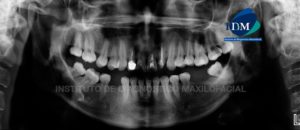

Paciente de sexo masculino con 38 años de edad, acude al Instituto de Diagnostico Maxilofacial para evaluación imagenologica de la pieza 27. A la evaluación